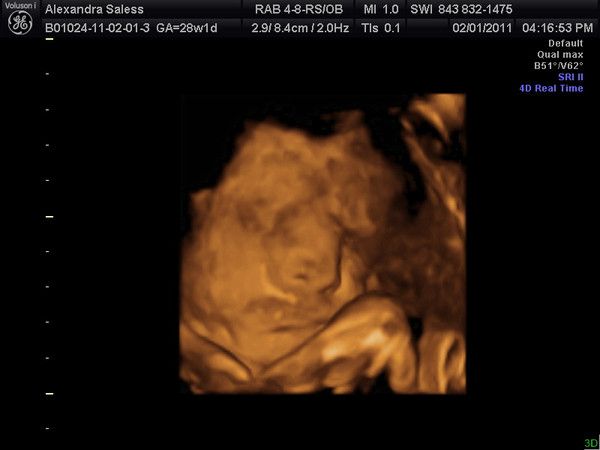

16W 4T Lexabailey's zweites US-Bild!

12.11.2010

Herzschlag war 143 bpm

So wie es aussieht ist es ein Maedchen (zu 95%)